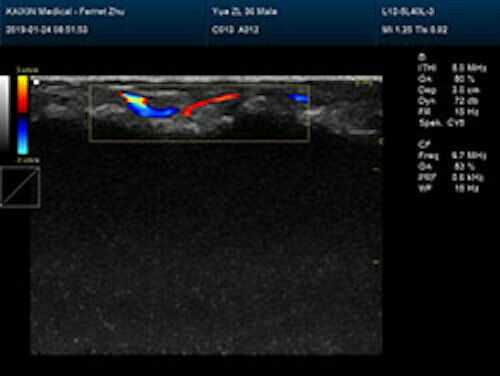

| Rich clinical application function • B+CF (Dual Images) • B+CF/PDI/DPDI+PW (Triplex) • Convex extended imaging technology • Linear array deflection/Trapezoidal imaging technology • Spatial compound Imaging technology • Panoramic imaging technology (optional) • 3D/4D imaging technology (optional) • Speckle noise removal technology • Pulse inversion tissue harmonic imaging technology (iTHI) |